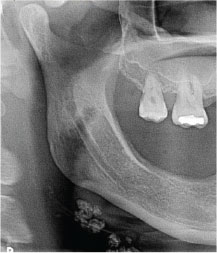

2. What condition can be seen in the following X ray? ( Open arrow)